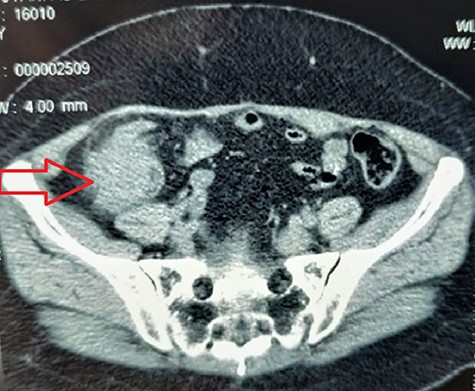

Two years later, she was admitted to the emergency department (ED) for acute bowel obstruction, with generalized abdominal pains, worsen in the right iliac fossa (RIF) associated with vomiting of gastric content, and without passage of stools or flatus. On physical examination, her vital signs were stable. Abdominal examination revealed a slight tenderness in the RIF, exaggerated bowel sounds with a 4 cm × 4 cm hard mobile lump in the RIF. Digital rectal examination revealed an empty rectal bowel. All the lymph node areas were disease-free. In the ED, abdominal computerized tomography (CT) scan revealed an intraluminal-caecal mass, measuring 43 mm in diameter, rounded in shape, tissue density, homogeneous, discreetly enhanced by the contrast product with no distant metastatic spread (Fig. 1).